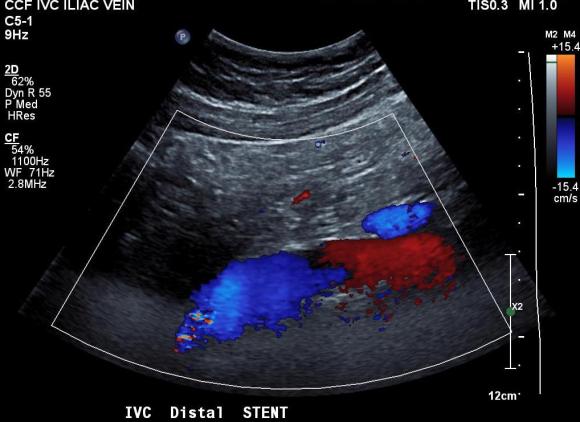

The patient was discharged after procedure on a baby aspirin only. He subsequently underwent laparoscopic inguinal herniorrhaphy and returned to my clinic about a month later. His followup duplex showed a widely patent stent and normal flows in the left iliac venous system.